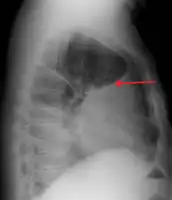

Anteroposterior chest X-ray of a pleural effusion. The A arrow shows fluid layering in the right pleural cavity. The B arrow shows the normal width of the lung in the cavity